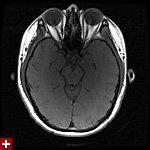

once i got back home and checked out my scans in osirix (the mac os x application to view DICOM medical imaging slides), i was blown away. talk about invasive: you haven't seen intimate until you've looked at photos of the inside of your body. the coolest part is since the scans were done in cross-sections, i can animate the scans so it looks like the beam is passing through my neck and head (all 800+ images). i've always known that inside my body was all sorts of muscles and veins and organs, but i guess i was hoping for something less messy, maybe circuit boards and memory chips instead. i know MRI's were first used in the late 60's, but this is my first time experiencing the technology in-person and it's pretty amazing. talk about futuristic! to be able to see with so much detail the insides of my body without having to cut me open! if scientists can do this, what else can they do? my only regret is they only imaged me from my shoulder up. i'd love to have a full-body scan. maybe i can fake some sort of internal injury and get my doctor to okay the procedure. i recommend anyone who's never had an MRI done to do so when they have the chance.

speaking of doctors, the main reason why i was at MGH this morning was for a follow-up appointment with my doctor. he basically told me that my MRI scans were fine as well as my blood work (he wrote me a letter a few weeks ago, so i already knew the news). since the pain in my neck had already disappeared,